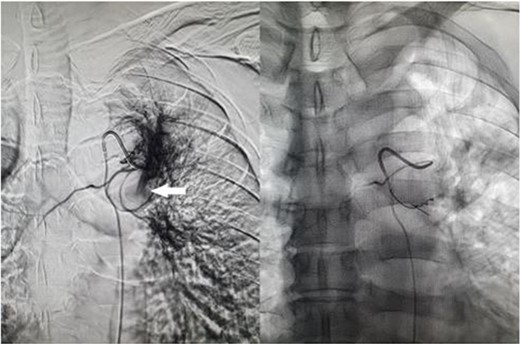

A 57-year-old male presented to the Emergency Department unwell with central chest pain, dyspnoea, and haemoptysis. CT pulmonary angiogram demonstrated bilateral cavitating pneumonia. Irregular nonenhancement of a segmental pulmonary artery in the left upper lobe was also noted (Fig. 1). CT thorax in systemic arterial phase demonstrated enhancement of this segmental branch in the left upper lobe (Fig. 1). These findings are due to reversal of flow in the pulmonary artery branch due to higher pressure blood from the bronchial artery passing through the fistula. The patient was brought to interventional radiology for further investigation and management. An initial nonselective descending aorta angiogram demonstrated the bronchial artery-pulmonary artery fistula in the left upper lobe. Selective cannulation of the enlarged left bronchial artery was then performed followed by microcatheter cannulation of the main feeding vessels to the fistula. The vessels were embolized to stasis with 400-μm microparticles (Embozene 400) and microcoils (Fig. 2). The patient tolerated the procedure well and had an uncomplicated postprocedural course. Pansensitive tuberculosis detected on sputum sample. Treatment with Rifater, pyridoxine, and ethambutol were commenced. No further episodes of haemoptysis have been noted to date on clinical follow-up.

Fluoroscopic image of bronchial artery catheterization and angiogram (left); flow of contrast into the pulmonary artery branch (white arrow) which quickly dissipates, and postembolisation image (right) with microcoils in the treated artery.